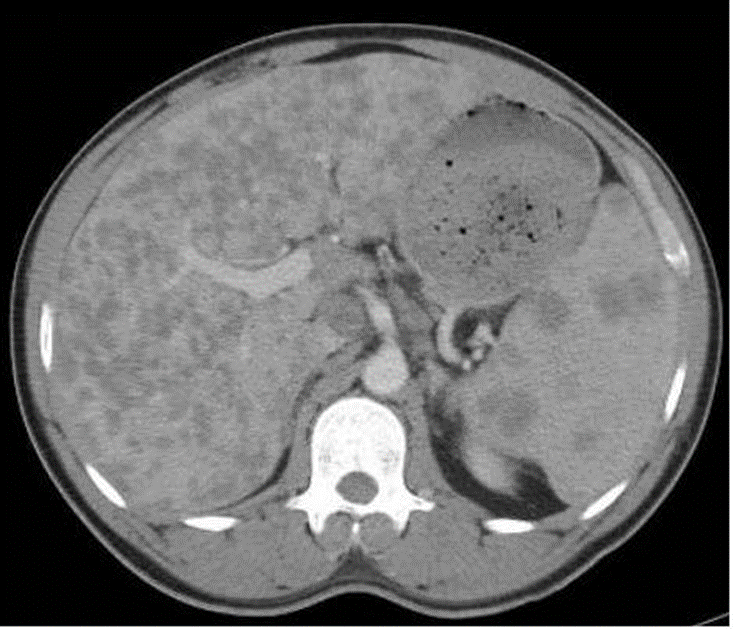

Figure 1.The CT scan of the abdomen and pelvis (Figures 2 and 3) showed an enlarged liver almost completely replaced by multiple low-attenuation lesions, none larger than 20 to 30 mm. The spleen was also enlarged, with multiple lesions measuring up to 20 mm. Extensive enlarged upper abdominal, periportal, and retroperitoneal lymph nodes were noted. These radiographic findings were suggestive of sarcoidosis or lymphoma.

Figure 2

Of note, hepatic involvement occurs in most patients with sarcoidosis. Hepatic sarcoidosis is approximately twice as common in the African American population than in the white population.3-5 Approximately 50% to 65% of patients with sarcoidosis will have granulomas on liver biopsy, but only 5% to 15% of patients have symptomatic hepatic sarcoidosis.4,6,7 Most are asymptomatic and only have biochemical abnormalities such as elevated alkaline phosphatase and γ-glutamyltransferase levels. Hepatomegaly is noted in 5% to 15% of patients.3,4 Typical CT findings are hepatosplenomegaly and numerous hypodense nodular lesions ranging in size from 1 mm to 3 cm.8,9 Gastroenterological involvement is found in 1% of cases and mostly manifests as gastric ulceration or mural infiltration.10 Liver biopsy is recommended when laboratory test results show moderate or severe liver abnormalities of more than 3 times the upper limit of normal.11